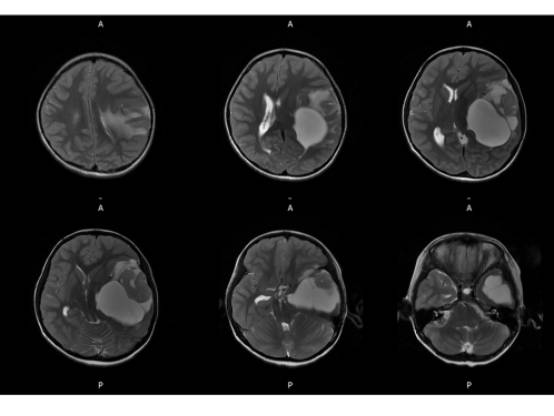

MR平扫及增强示:

MR

左侧颞叶见大块状等长T1等长T2异常信号,FLAIR呈高新,DWI(b=1000)实质部分呈稍高信号,ADC实质部分呈等信号,边界尚清,周围脑实质受压。注入GD-DTPA后病变实质部分呈明显强化。